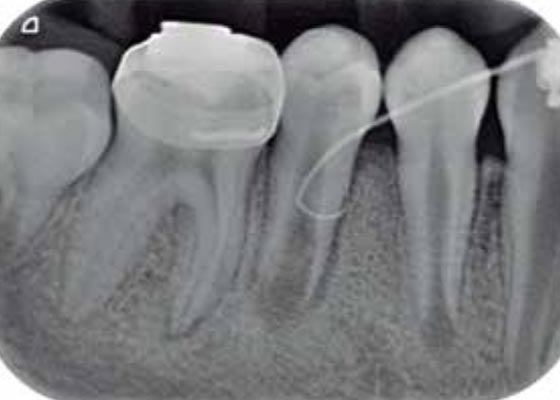

Imágenes: Endodoncia en un molar inferior izquierdo